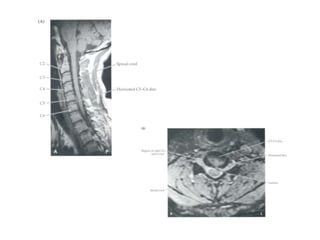

RAIZES NERVOSAS XVERTÉBRAS, DISCOS E LIGAMENTOS